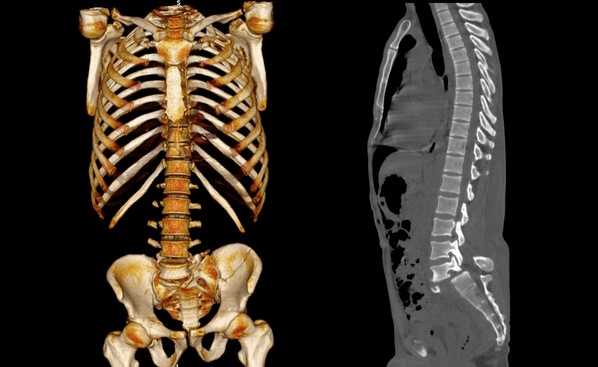

Сколиоз позвоночника на снимках КТ

Перелом со смещением в области крестцово-копчикового отдела (компьютерная томография)